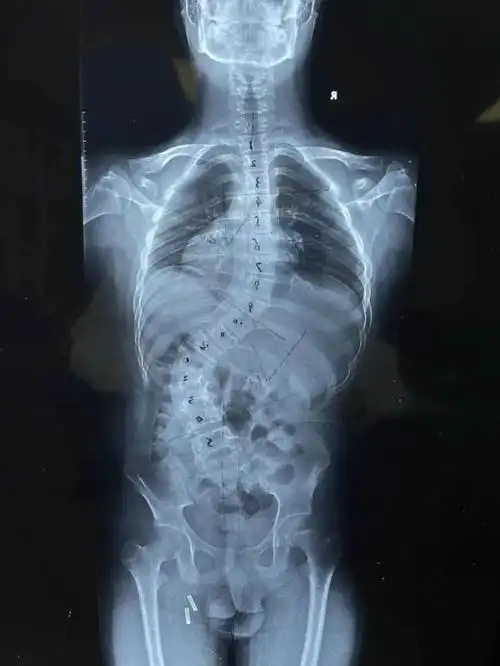

15岁男孩脊柱侧弯达60度医生提醒孩子出现此类情况需当心